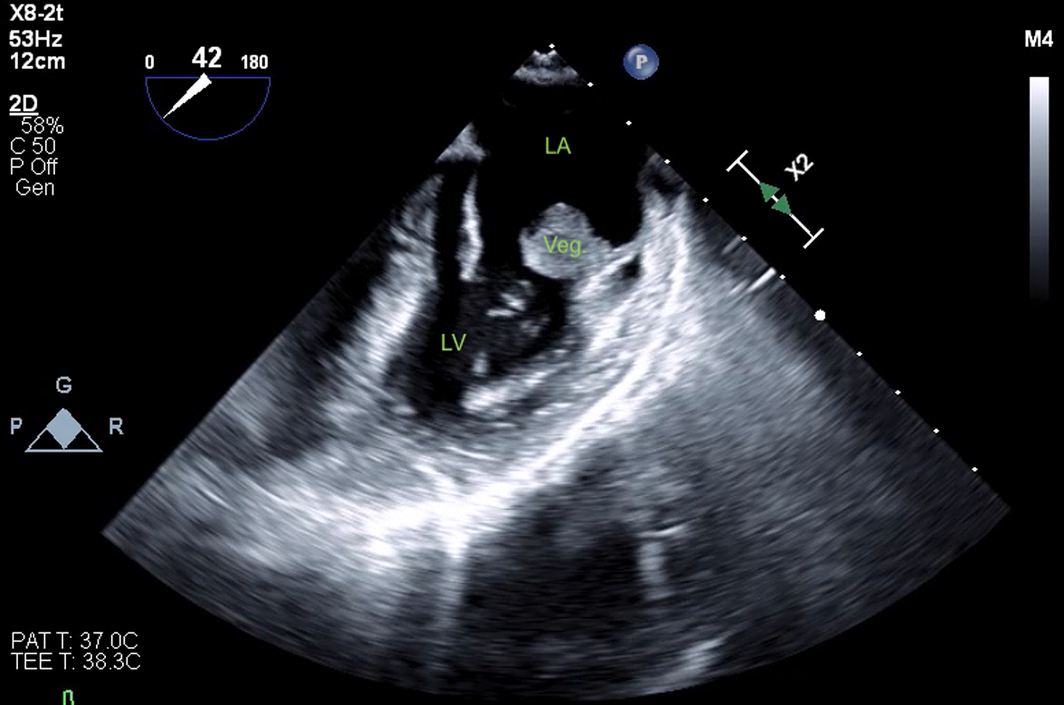

The patient's cardiovascular examination was unremarkable, without stigmata of infective endocarditis or murmur, and a normal electrocardiogram. However, owing to concern regarding infective endocarditis, he proceeded to a transthoracic echocardiogram, which revealed a large, mobile mass fixed to the mitral valve. This was further characterised by transoesophageal echocardiography as a 13 mm × 12 mm vegetation on the anterolateral commissure, associated with progressive mitral regurgitation (Box 1). Left ventricular function was preserved with no other valvular abnormalities. Magnetic resonance imaging suggested a cerebral embolic phenomenon; however, there were no clinical sequelae of stroke. Coronary angiography, as part of surgical workup, revealed no significant coronary artery disease. Despite one week of antimicrobials, following multidisciplinary team discussion, the patient was managed surgically with a vegetectomy (Box 2) and mitral valve repair (bovine patch), curtailing the need for metallic valve replacement, followed by six weeks of IV benzylpenicillin. Despite a stable post‐operative period, the patient presented again with dyspnoea and peripheral oedema. He was found to have recurrence of moderate mitral regurgitation. In consultation with the multidisciplinary team, he was managed medically with diuretics and prolonged infection surveillance. He remains stable with improved inflammatory markers and mild mitral regurgitation on the most recent transthoracic echocardiogram.